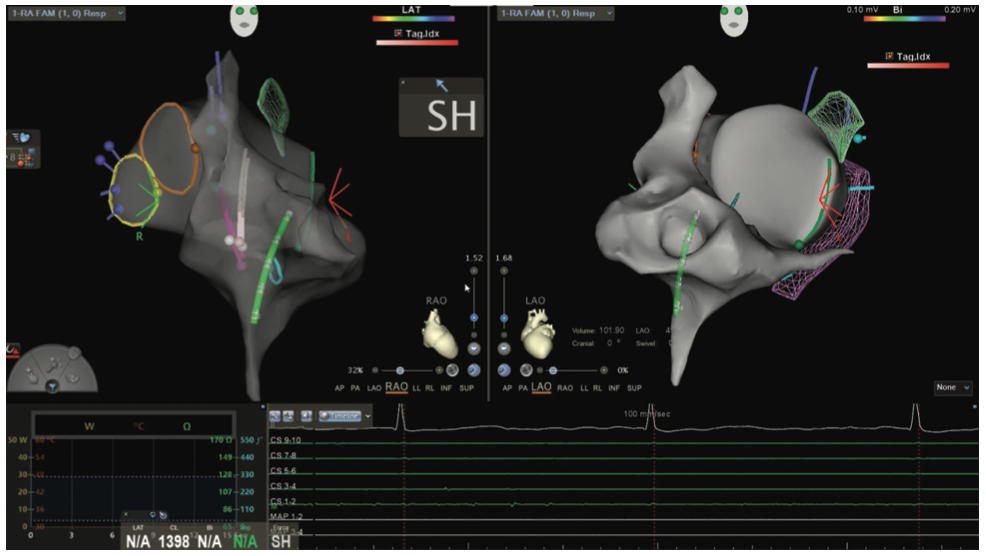

Figures/Videos 1-10 demonstrate the process of navigation from groin access to the heart to create biatrial geometry, localize the esophagus, and gain transseptal access. Many currently practicing electrophysiologists use very little fluoroscopy to map and ablate the left atrium (LA) with the current multielectrode catheters and EAM systems once transseptal access is obtained.

Figure 17 illustrates the usefulness of using the clipping plane in the right atrium to see the septal wall and CS os for slow pathway ablation. Both RAO and LAO views are shown and the distance from the successful slow pathway lesions and the AV node (yellow) was 15.9 mm.